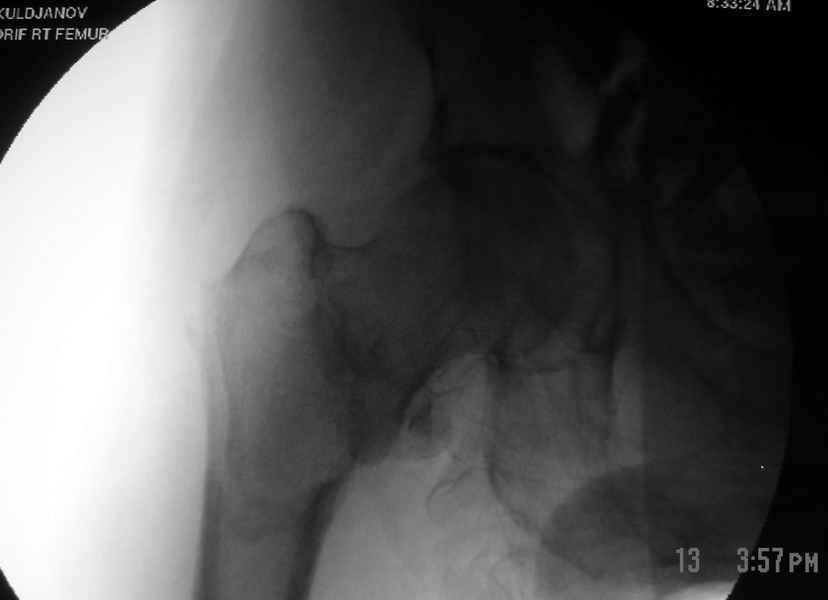

Другие случаи: применение Synthes TTFN (trochanteric titanium femoral nail) и Blade Plate (угловая пластина), так что много различных вариантов фиксации подобных переломов.